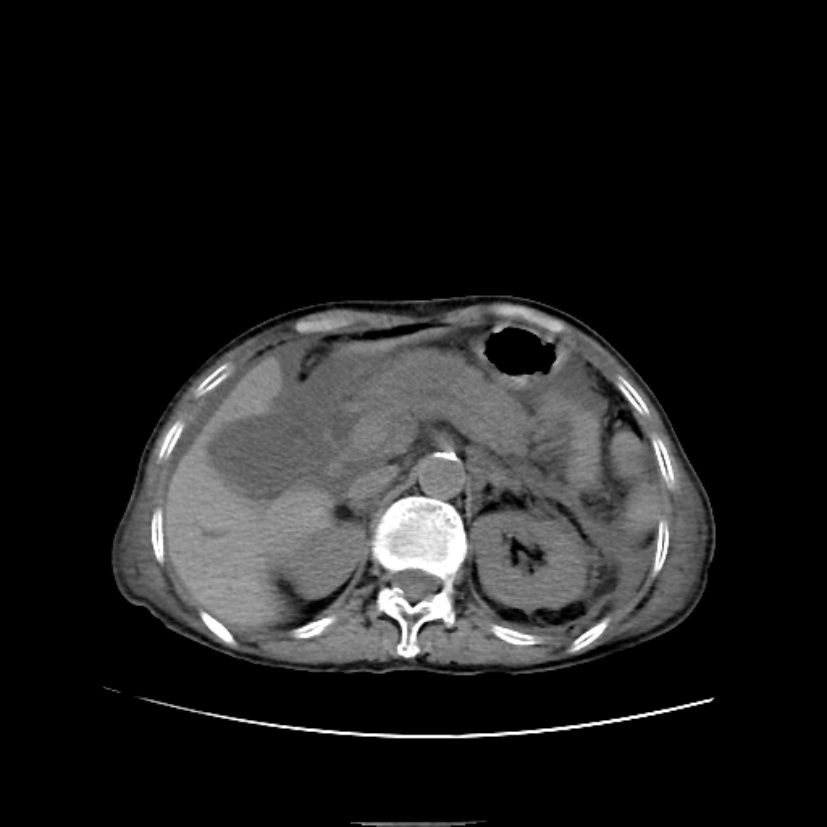

Figure 5. A 29-year-old male with a Balthazar score of 2 and CRP of 9.96 mg/L upon admission. Abdominal CT axial scan shows slight enlargement of the pancreas, increased fat density around the pancreas with striped and reticular patterns, and no obvious fluid accumulation. The nomogram predicts a 4% risk of composite severe outcomes. The patient did not develop composite severe outcomes during hospitalization and was discharged after symptomatic treatment

5. 男,29岁,入院时Balthazar评分2分,CRP 9.96 mg/L;上腹部CT轴位平扫示:胰腺体积稍增大,胰周脂肪密度增高并见条纹状、网状影,无明显积液。列线图预测复合重症风险约4%,住院期间未发生复合重症结局,患者对症治疗后出院